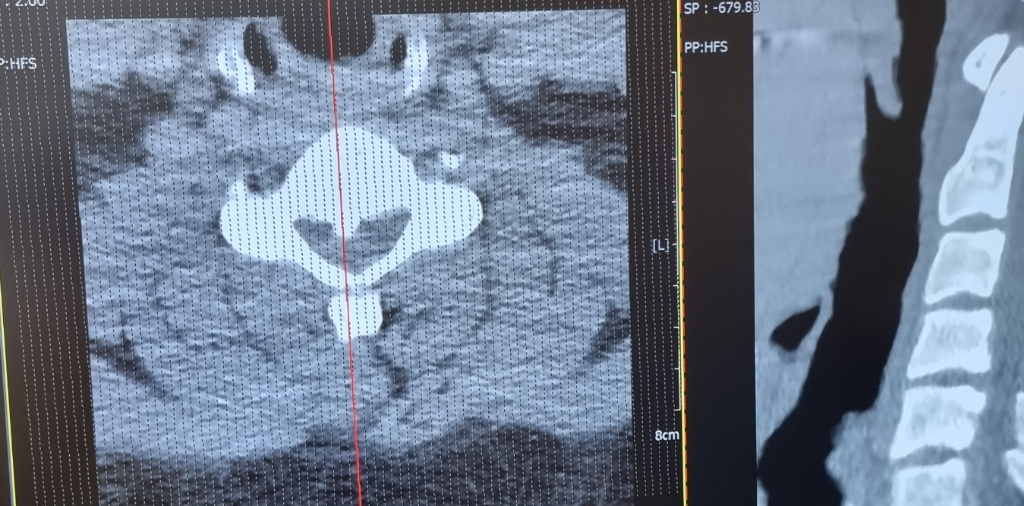

증상과 척수병증의 발병 여부가 중요합니다.